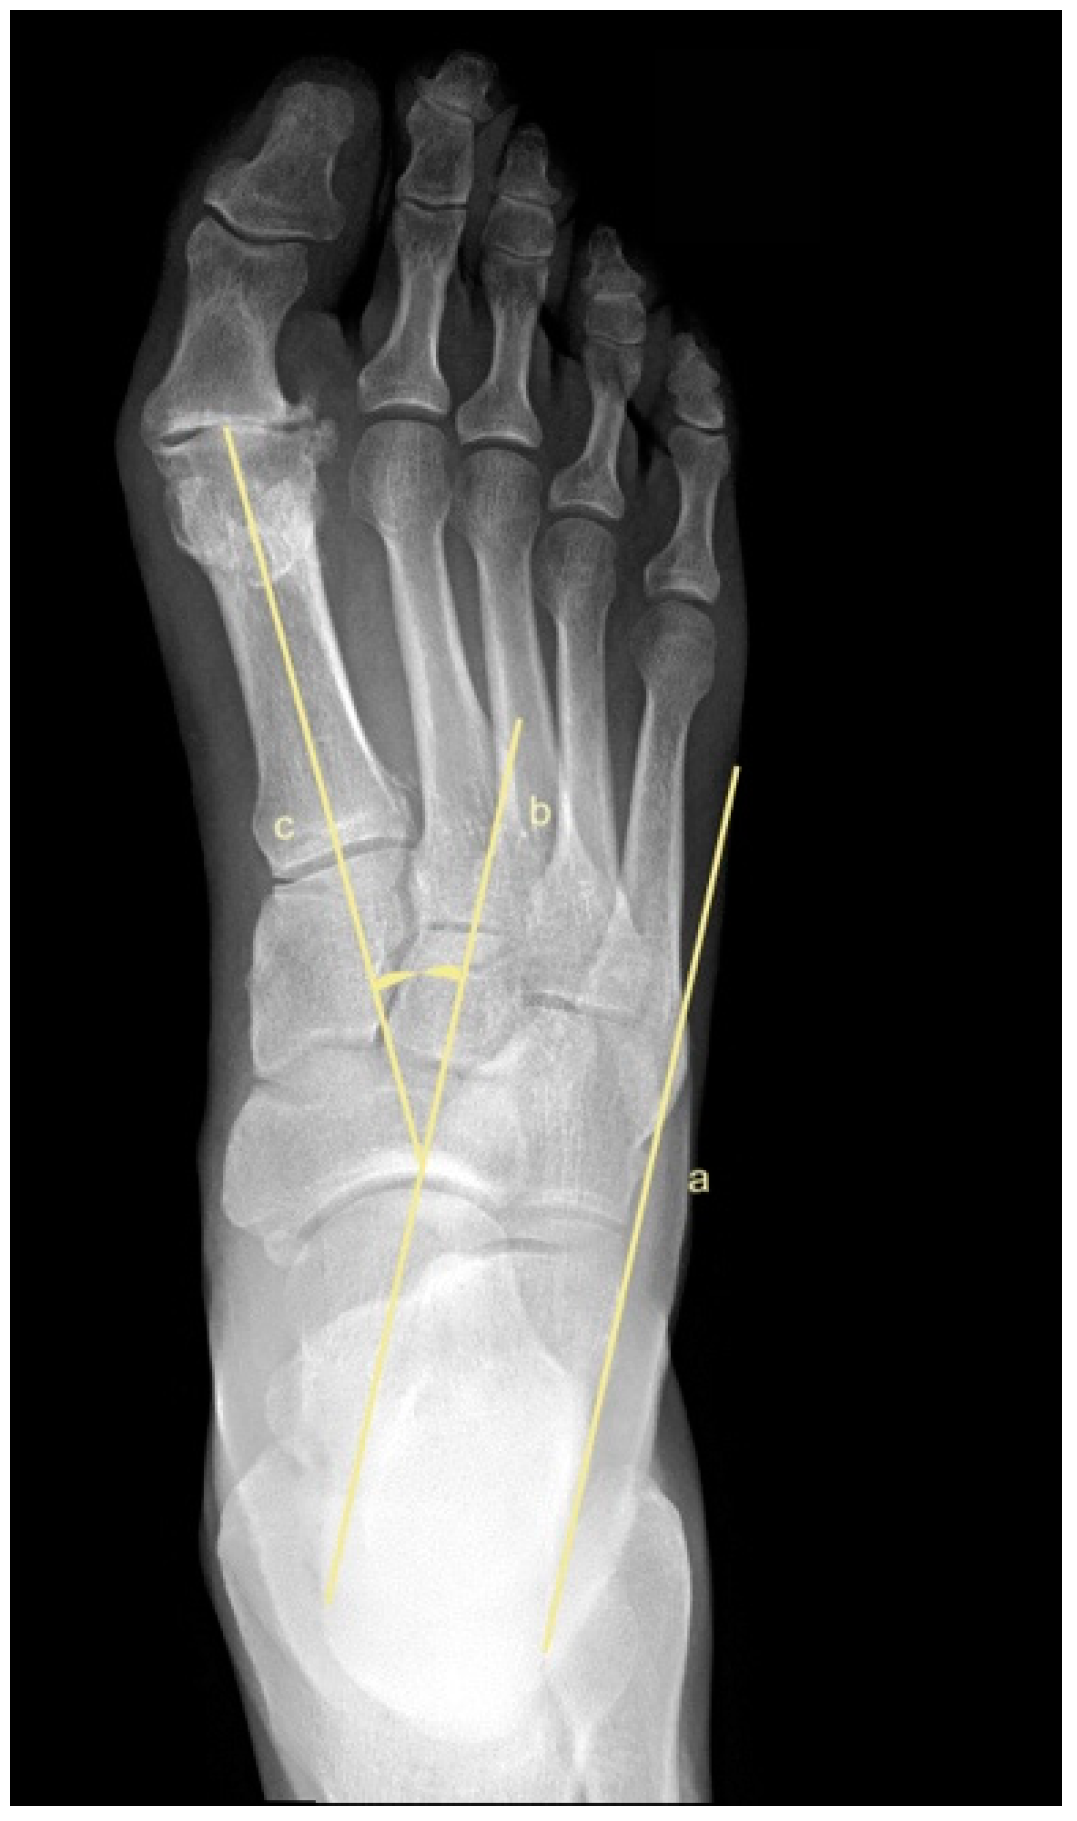

2.5. Metatarsus Adductus Measurements

- Sgarlato, T.E. Compendium of Podiatric Biomechanics; California College of Podiatric Medicine: San Francisco, CA, USA, 1971. [Google Scholar]

- Weissman, S.D. (Ed.) Biomechanically acquired foot types. In Radiology of the Foot; Williams and Wilkens: Baltimore, MD, USA, 1989. [Google Scholar]

- Gentili, A.; Masih, S.; Yao, L.; Seeger, L.L. Pictorial review: Foot axes and angles. Br. J. Radiol. 1996, 69, 968–974. [Google Scholar] [CrossRef]

- Ganley, J.V.; Ganley, T.J. Metatarsus adductus deformity. In Comprehensive Textbook of Foot Surgery, 2nd ed.; Wilkins, W., Ed.; Williams and Wilkens: Baltimore, MD, USA, 1992; pp. 829–852. [Google Scholar]

- Engel, E.; Erlick, N.; Krems, I. A simplified metatarsus adductus angle. J. Am. Podiatry Assoc. 1983, 73, 620–628. [Google Scholar]

- Simons, G.W. Analytical radiography of club feet. J. Bone Jt. Surg. Br. Vol. 1977, 59, 485–489. [Google Scholar] [CrossRef] [PubMed]

- Laaveg, S.J.; Ponseti, I.V. Long-term results of treatment of congenital club foot. J. Bone Jt. Surg. Am. Vol. 1980, 62, 23–31. [Google Scholar] [CrossRef]

- Kilmartin, T.E.; Flintham, C. Hallux valgus surgery: A simple method for evaluating the first-second intermetatarsal angle in the presence of metatarsus adductus. J. Foot Ankle Surg. 2003, 42, 165–166. [Google Scholar] [CrossRef]

- Dawoodi, A.I.S.; Perera, A. Radiological assessment of metatarsus adductus. Foot Ankle Surg. 2012, 18, 1–8. [Google Scholar] [CrossRef]